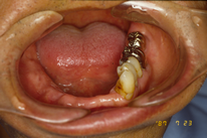

左下の歯が5本残っている。 |

部分入れ歯(金属床) |